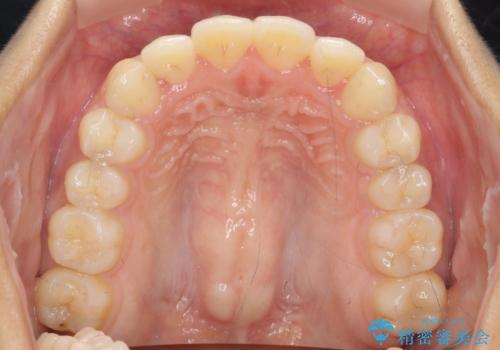

前歯のねじれ、すれ違いを改善 部分ワイヤー+マウスピース矯正

前歯のすれ違いが改善することで噛みやすくなった。と矯正治療の結果に満足いただくことができました。

上顎前歯のみの部分ワイヤー治療を約6ヶ月行い、ねじれの問題を解決したのち、マウスピース矯正で細かな歯列を整えていきます。